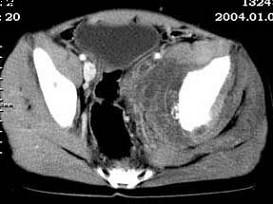

问题 女,35岁,7个月前无诱因出现左下肢阵发性疼痛,左骶髂部活动受限,进行性加重,排便困难,请根据所提供的图像,选择最佳选项 ( )

选项 A、转移瘤 B、滑膜肉瘤 C、软骨肉瘤 D、骨巨细胞瘤 E、脊索瘤

答案 B